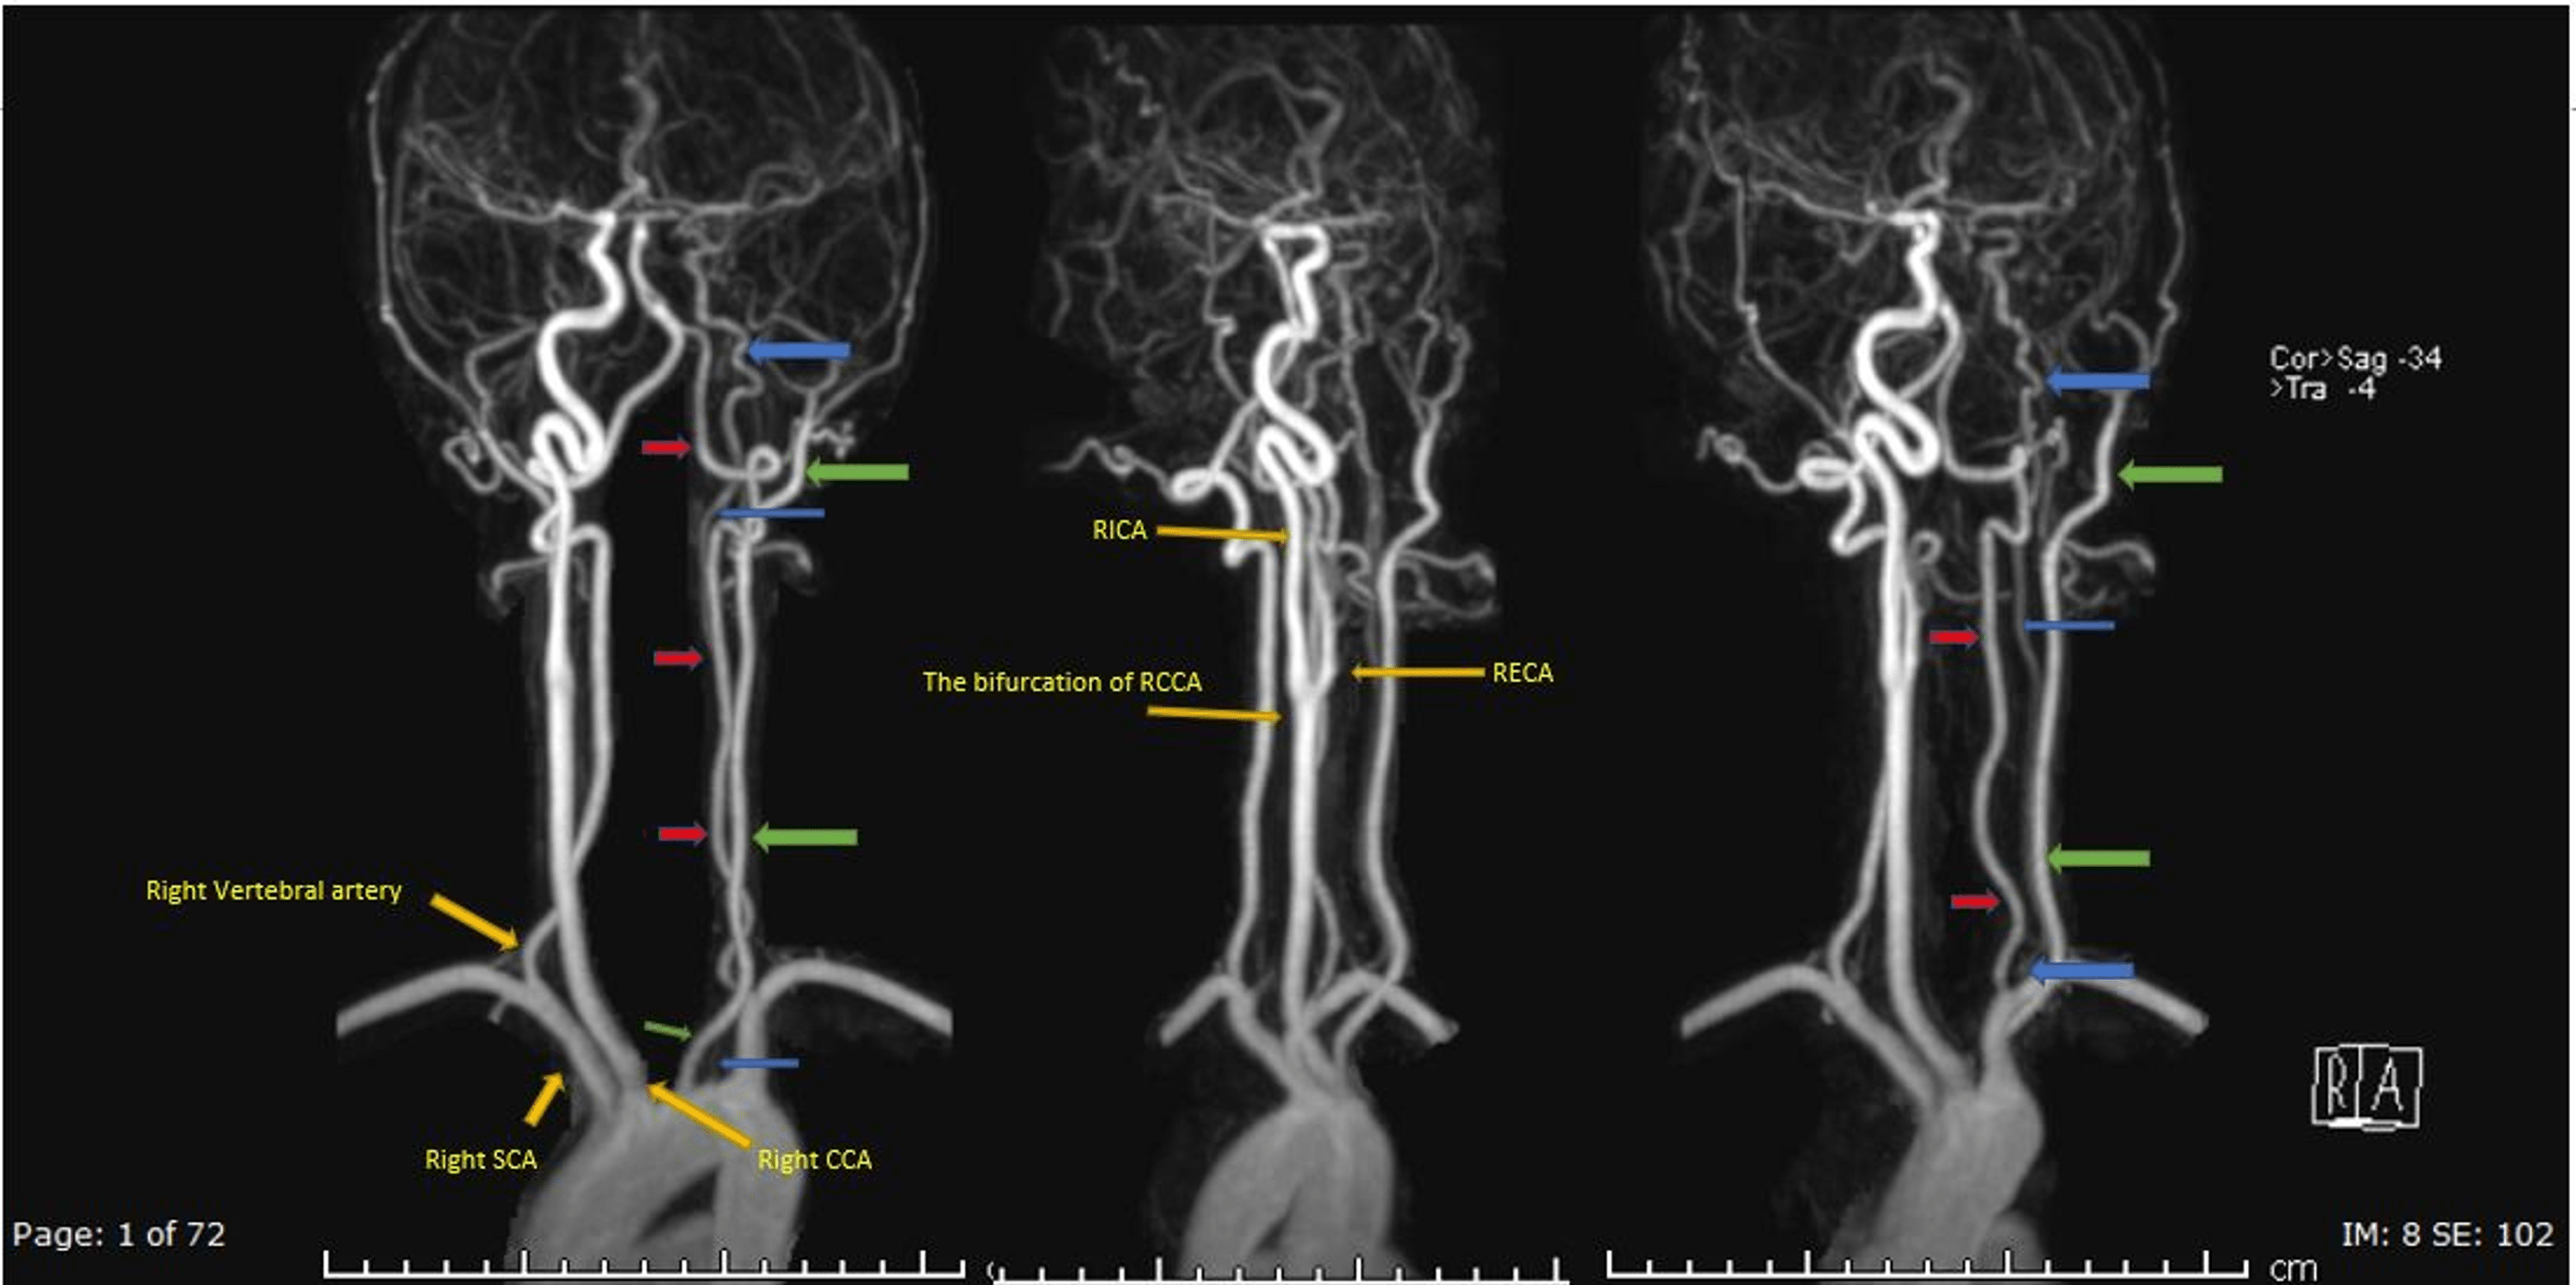

From www.alamy.com

CTA brain and carotid artery or CT angiography of the brain 3D Stethoscope Carotid Artery — in carotid stenting, a surgeon sends a long, hollow tube, known as a catheter, through the arteries to the narrowed carotid artery in the neck. This assessment provides information about. Like water rushing along a bubbling brook, turbulent. But, the results of this test can be misleading. — narrowing of a carotid artery produces turbulent blood flow.. Stethoscope Carotid Artery.

CTA brain and carotid artery or CT angiography of the brain 3D Stethoscope Carotid Artery But, the results of this test can be misleading. This assessment provides information about. Bruit sounds may not always be present, even when carotid artery disease is severe. carotid artery disease may be suspected if a doctor hears a whooshing sound (called a bruit) while listening to a patient’s neck with a stethoscope during a checkup. assessment of. Stethoscope Carotid Artery.